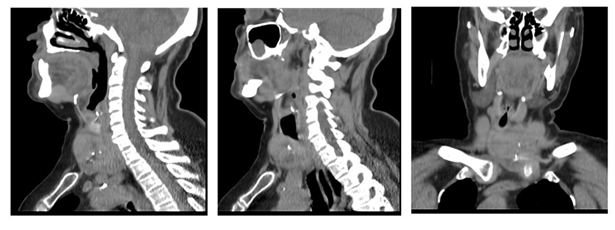

The ct showed a voluminous mass with an epicenter in the li measuring 62 x 72 x 53 mm. On its right lateral side, it contacts and displaces the visceral axis of the neck. It determined stenosis of the trachea with a residual lumen of up to 9 mm (

figures 4 and 5).

Figure 4: ct, axial section showing goiter mainly in the left lobe with displacement of the visceral axis of the neck and tracheal lumen stenosis

Figure 5: ct, sagittal and coronal section showing substernal goiter extending below the brachiocephalic vessels with displacement and narrowing of the tracheal lumen Thyroid function was normal.